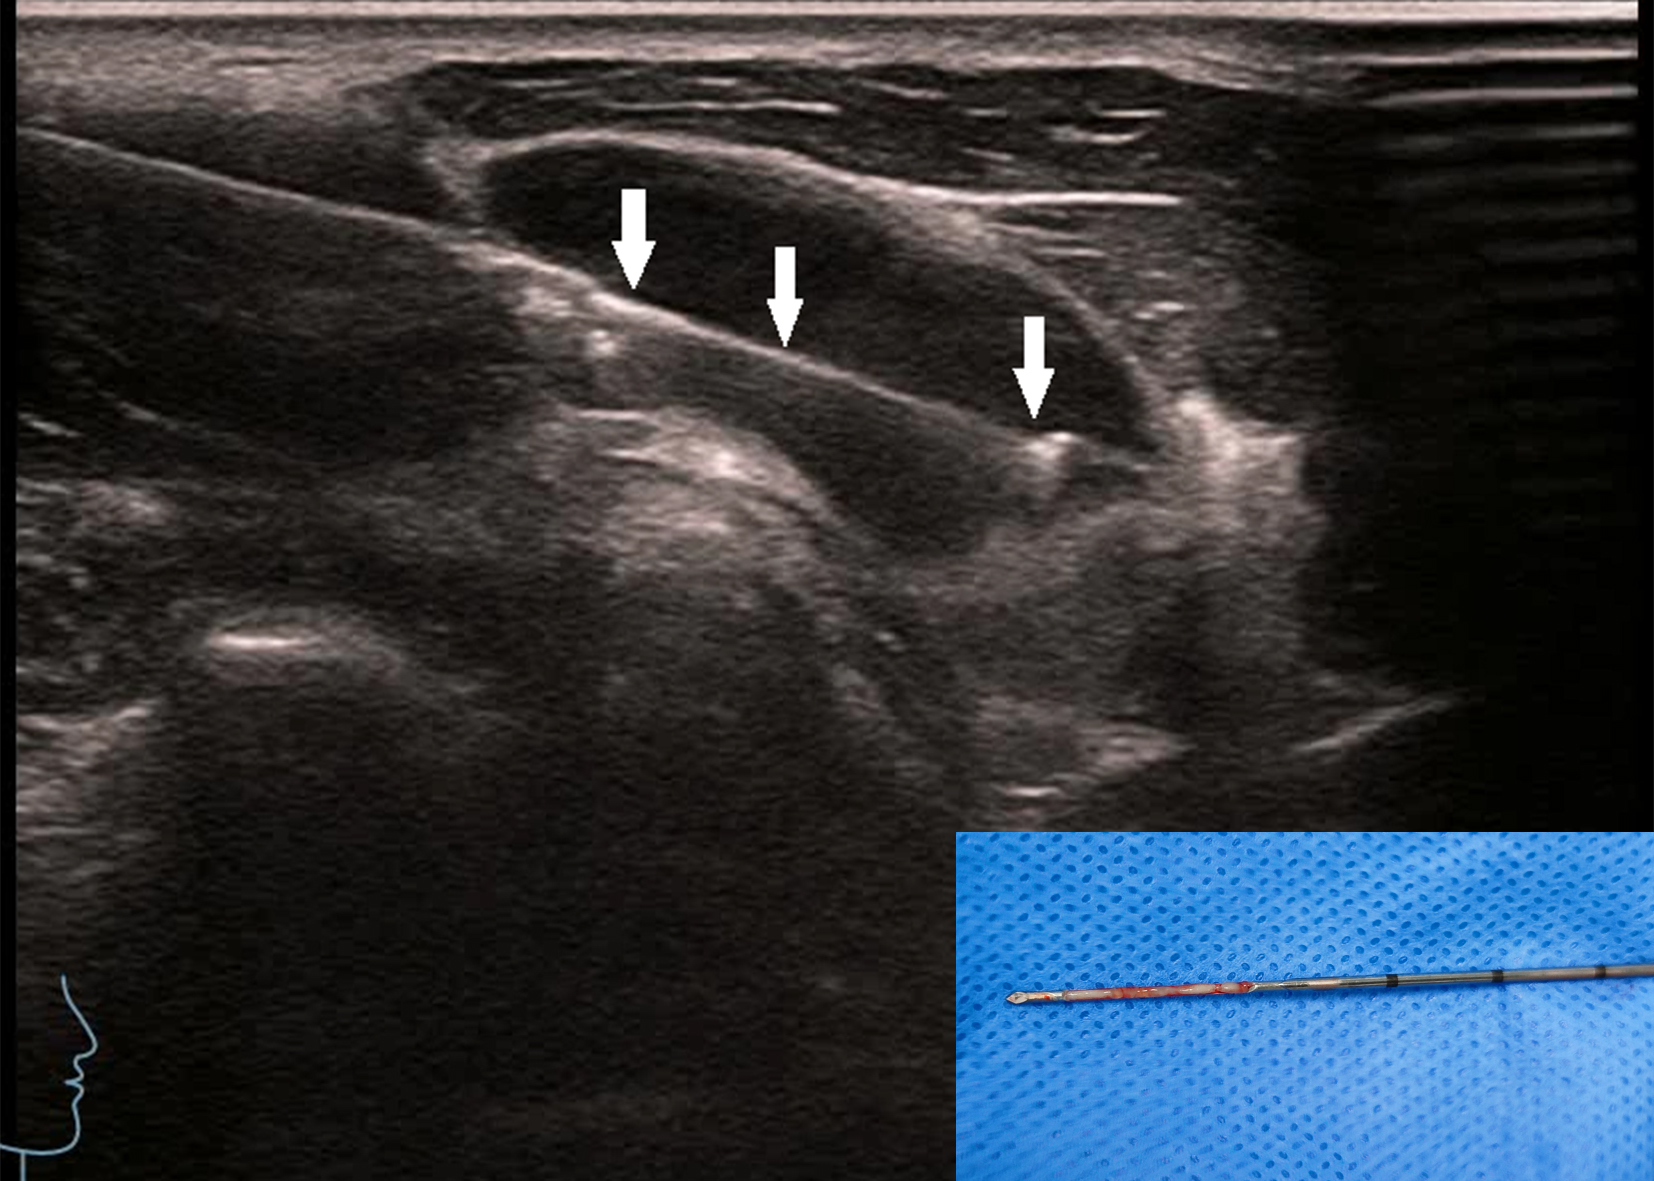

Figure 4

The patient is the same as shown in Figure 3. The biopsy was taken along the long axis of the lymph node. The arrow shows the core needle biopsy needle groove, and the image on the right shows good specimen integrity.